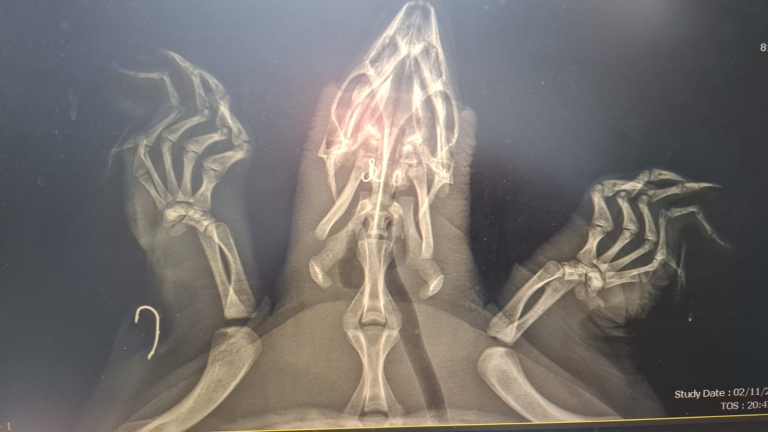

במרכז הארצי להצלת צבי ים נלקח הצב לבדיקה רדיולוגית במרפאת "כל חי" ברחובות. צילום הרנטגן חשף את חומרת הפציעה: קרס אחד היה נעוץ בוושט וקרס נוסף בגפה השמאלית הקדמית של הצב.

הווטרינר ד"ר צחי אייזנברג וגיא איבגי, המטפל הראשי של מרכז ההצלה, ביצעו הליך מוצלח להוצאת שני הקרסים. לאחר הניתוח נשלח הצב להמשך התאוששות והשגחה בבריכת שיקום לצבים רכים במרכז ההצלה במכמורת.